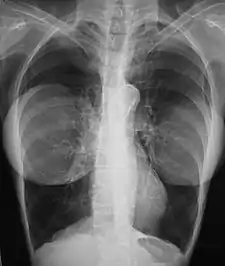

Mammography

The presence of radiologically opaque breast implants (either saline or silicone) might interfere with the radiographic sensitivity of the mammograph, that is, the image might not show any tumor(s) present. In this case, an Eklund view mammogram is required to ascertain either the presence or the absence of a cancerous tumor, wherein the breast implant is manually displaced against the chest wall and the breast is pulled forward, so that the mammograph can visualize a greater volume of the internal tissues; nonetheless, approximately one-third of the breast tissue remains inadequately visualized, resulting in an increased incidence of mammograms with false-negative results.[110][111]

The breast cancer studies Cancer in the Augmented Breast: Diagnosis and Prognosis (1993) and Breast Cancer after Augmentation Mammoplasty (2001) of women with breast implant prostheses reported no significant differences in disease-stage at the time of the diagnosis of cancer; prognoses are similar in both groups of women, with augmented patients at a lower risk for subsequent cancer recurrence or death.[112][113] Conversely, the use of implants for breast reconstruction after breast cancer mastectomy appears to have no negative effect upon the incidence of cancer-related death.[114] That patients with breast implants are more often diagnosed with palpable—but not larger—tumors indicates that equal-sized tumors might be more readily palpated in augmented patients, which might compensate for the impaired mammogram images.[115] The ready palpability of the breast-cancer tumor(s) is consequent to breast tissue thinning by compression, innately in smaller breasts a priori (because they have lesser tissue volumes), and that the implant serves as a radio-opaque base against which a cancerous tumor can be differentiated.[116]

The breast implant has no clinical bearing upon lumpectomy breast-conservation surgery for women who developed breast cancer after the implantation procedure, nor does the breast implant interfere with external beam radiation treatments (XRT); moreover, the post-treatment incidence of breast-tissue fibrosis is common, and thus a consequent increased rate of capsular contracture.[117] There is tentative evidence that women who have had breast augmentation, have worse breast cancer prognosis.[118] The use of implants for breast reconstruction after breast cancer mastectomy appears to have no negative effect upon cancer-related death.[114][119]

There have been multiple reported cases of other adverse effects of mammography of women with breast implants; ruptures resulting from pressure exerted on the breast implant make up a majority of these cases.[120] Compression may also lead to pain or exacerbate already existing pain in the breasts.[120]